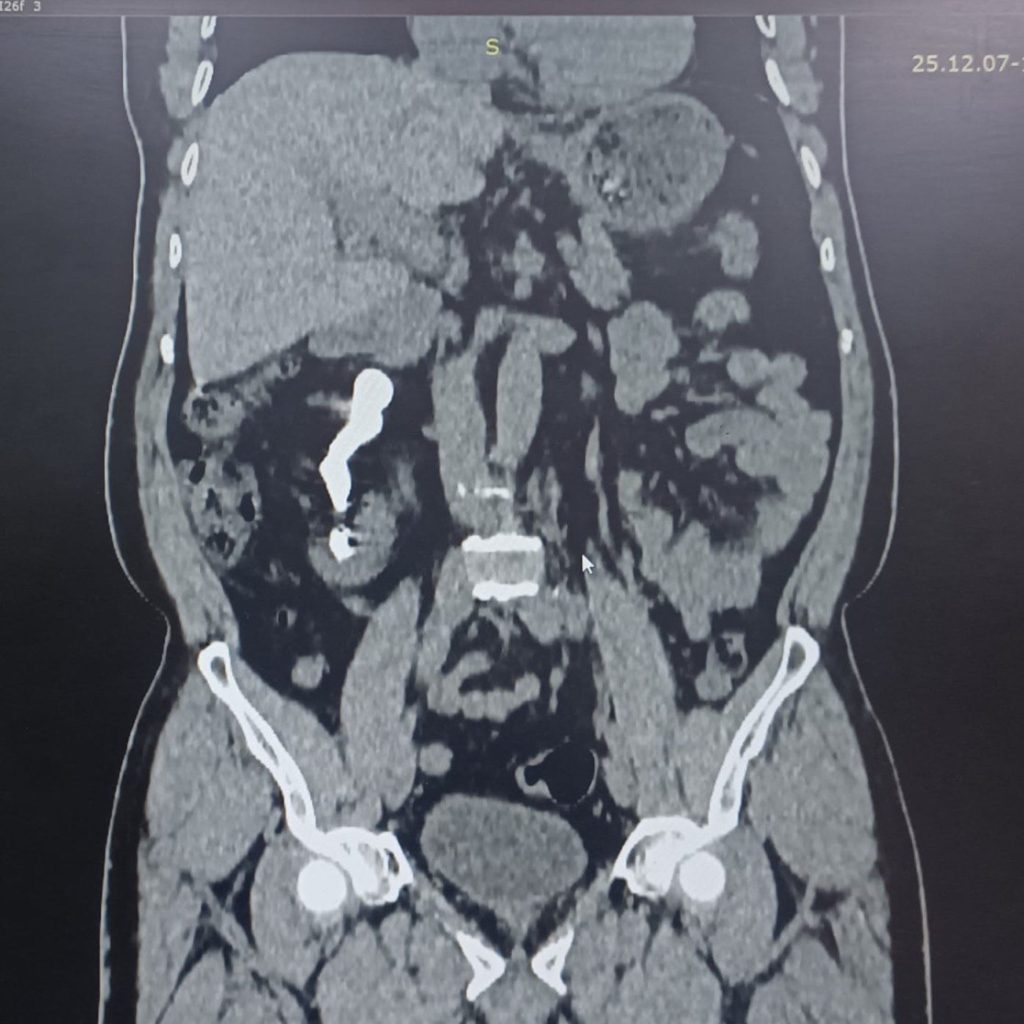

بعد معاناة امتدت لأكثر من خمس سنوات، وضع خلالها الألم الكلوي المزمن وآلام الظهر المريض أمام تحدٍّ يومي قاسٍ، نجح فريق طبي متخصص في مستشفى الإمام الحجة (عج) الخيري في طيّ صفحة واحدة من أعقد الحالات الكلوية، عبر إجراء عملية ناظورية متقدمة لاستخراج حصاة من نوع قرن الأيل تجاوز حجمها 10 سم.

«تمكّنا، بفضل الله، من إجراء عملية ناظورية حديثة عبر الجلد، استخرجنا خلالها الحصاة بالكامل من خلال فتحة صغيرة لا تتجاوز 1 سم، دون الحاجة إلى أي فتح جراحي، وهو ما خفف كثيرًا من المخاطر وساعد على تسريع التعافي».